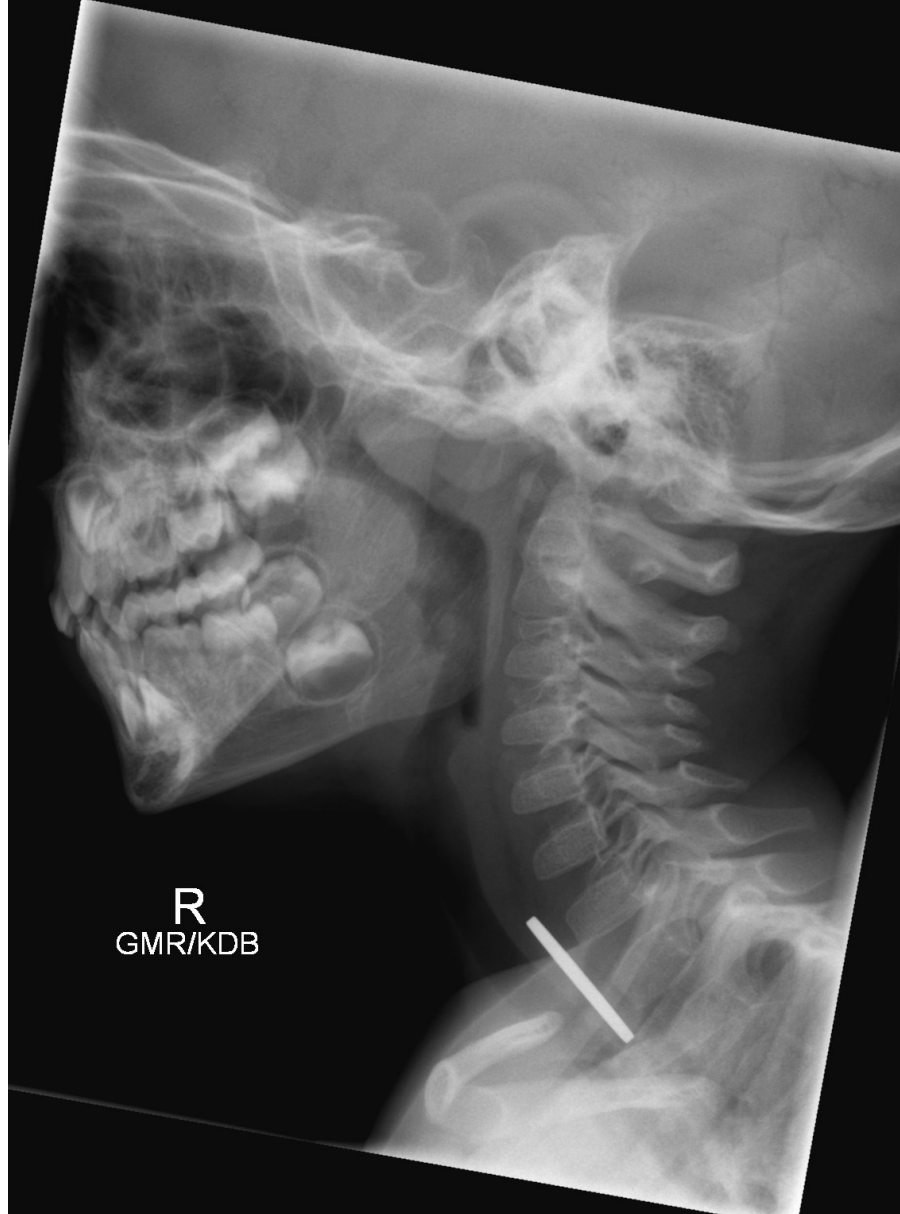

Q

what are the relevant features of this x ray

A

radio opague FB in oesophagus - likely coin

it is below laryngeal inlet and not obstructing trachea